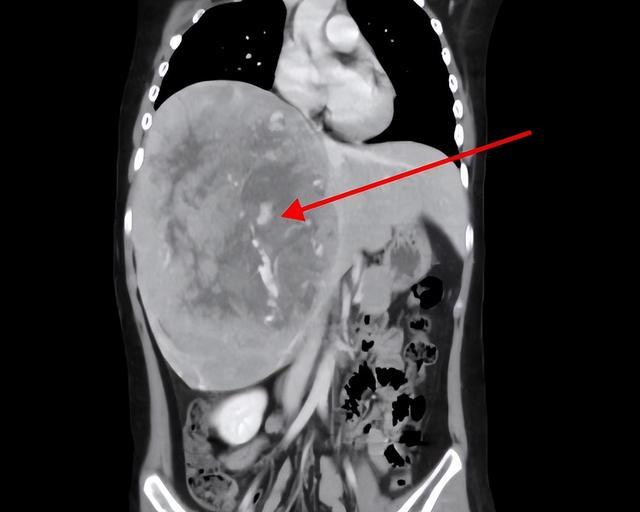

据该院急诊外科接诊医生王亮介绍,孩子入院时检查发现腹肌紧张,右上腹压痛,胸腹部增强CT提示:肝右叶肿块,考虑:肝母细胞瘤?合并肿瘤内出血。

(CT检查显示肝右叶巨大肿块)

手术中发现患儿右肝巨大占位性病变,约20cm*10cm*6cm大小,予以完全剥离,手术顺利,病理结果证实为“肝母细胞瘤”。术后转急诊重症监护室继续治疗。经过急诊科副主任、主任医师丁宁带领医护团队给予精心照护,患儿病情好转稳定,现已转出重症监护室,在急诊综合病房继续治疗。